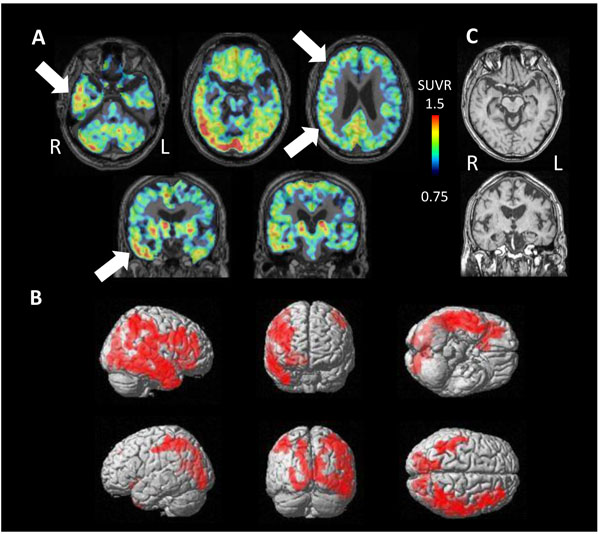

3.3. Regional SUVR of [11C]PBB3 in ANDE and HC

The SUVR of AGD and NFTPD was compared with that in HC. Significantly high accumulation was found in the parietal cortex, precuneus and the lateral temporal cortex of NFTPD (P<0.05) (Fig. 3).

To evaluate the effect of atrophy on apparent [11C]PBB3 accumulation, each side was analyzed separately in cases with AGD. In most cases, a great difference in [11C]PBB3 accumulation was seen between the sides, but no correlation was found between the side of atrophy and level of tau accumulation (Fig. 3).

In addition, the level of individual SUVR was compared with the distribution of tau accumulation in HC. The open square in Fig. (3) indicates significantly high accumulation in the parietal lobe, frontal lobe, and parahippocampal gyrus.

No correlation was found between MMSE and SUVR in AGD as well as in NFTPD.